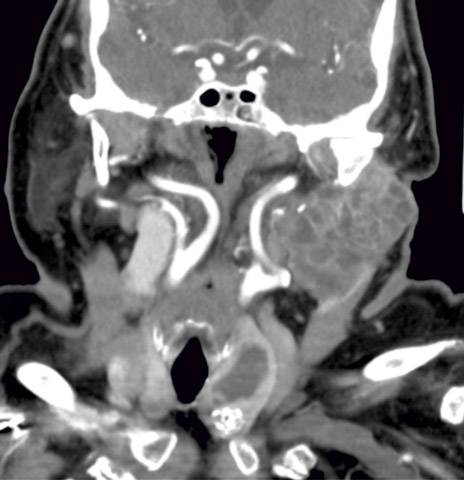

Különleges koponyasebészeti eljárást végeznek a Pécsi Tudományegyetem Klinikai Központban. Rendkívül bonyolult, oldalsó-koponyaalapi műtéteket végeznek a PTE KK fül-orr-gégészei és idegsebészei. A speciális eljárás Magyarországon jelenleg csak itt érhető el rendszeresen az érintett páciensek számára – tudatták sajtósaik.

Összetett speciális műtéteket végeznek a Pécsi Tudományegyetem Klinikai Központ Fül-Orr-Gégészeti és Fej-Nyaksebészeti Klinika, valamint az Idegsebészeti Klinika szakemberei az oldalsó koponyaalapi elváltozások kezelésében. A területen végzett műtétek hatalmas kihívás elé állítják az orvosokat, hiszen a beavatkozásokhoz komoly szakmai tapasztalatra és felkészültségre van szükség.

A kooperáció a fül és a halántékcsont jó-, és rosszindulatú elváltozásait, valamint a kisagy-híd szögleti daganatok különböző típusait kezeli a nemzetközi irányelvek szerint sebészeti és konzervatív módokon. Több alkalommal a műtét során hallásrehabilitációt is elvégzett a team egy különleges eszköz beültetésével, úgy nevezett cochlearis-implantációval.